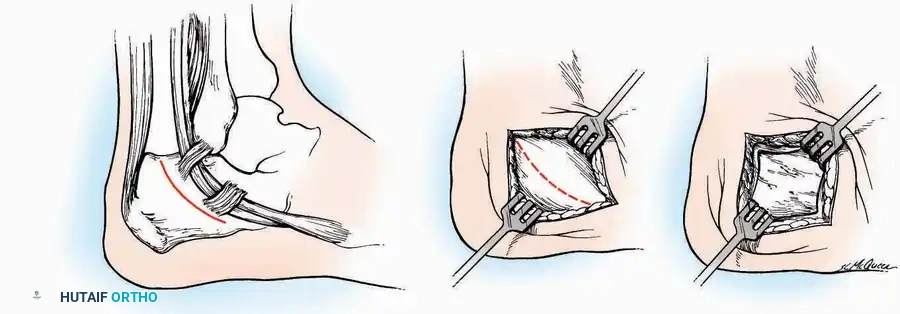

SURGICAL APPROACHES TO THE CALCANEUS

Approaches to the calcaneus are dictated by the pathology—trauma (intra-articular fractures) versus tumor/infection. Positioning is critical; while the prone position offers excellent bilateral access, the lateral decubitus or modified supine positions are more frequently utilized for unilateral trauma.

Lateral Approach (Extensile Lateral)

This is the workhorse approach for open reduction and internal fixation (ORIF) of displaced intra-articular calcaneal fractures.

Indications: ORIF of calcaneus fractures, lateral wall exostectomy, subtalar arthrodesis.

Positioning: Lateral decubitus with the operative leg up, or supine with a large bump under the ipsilateral hip to internally rotate the leg.

Surgical Technique:

* Incision: Begin the incision on the lateral margin of the Achilles tendon near its insertion. Extend it distally to a point 4 cm inferior and 2.5 cm anterior to the lateral malleolus. (For trauma, a classic L-shaped extensile incision is often used, dropping straight down anterior to the Achilles, then curving gently toward the base of the 5th metatarsal).

* Superficial Dissection: Divide the superficial and deep fasciae. It is imperative to create a "full-thickness" flap containing skin, subcutaneous fat, and periosteum to prevent flap necrosis.

* Nerve Protection: The sural nerve crosses the proximal and distal limbs of this approach. It must be identified and protected within the anterior flap.

* Deep Dissection: Isolate the peroneal tendons (longus and brevis). Incise and elevate the periosteum below the tendons to expose the lateral wall of the calcaneus.

* Tendon Management: If severe deformity or infection is present, the peroneal tendons may be divided via Z-plasty and repaired at the conclusion of the case, though this is rarely necessary in modern fracture care.